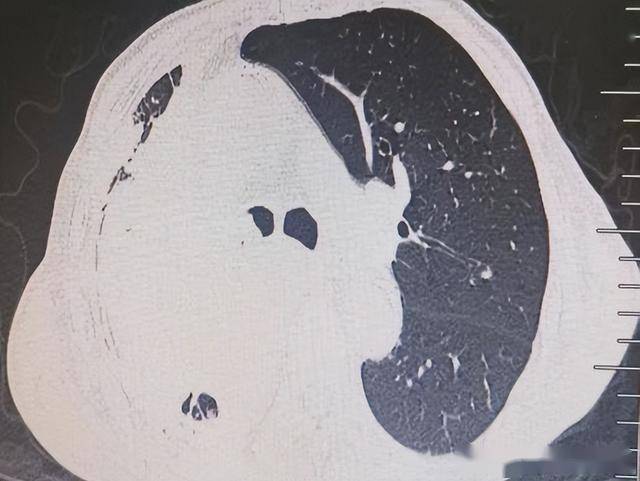

⋄ 2025年10月24日 行CT引导下经皮肺肿物穿刺活检术(微创、后续治疗方案制定的前提)。术后病理:高级别神经内分泌癌,倾向于小细胞神经内分泌癌可能。

治疗前:右主支气管完全堵塞

治疗后:右上支气管开通